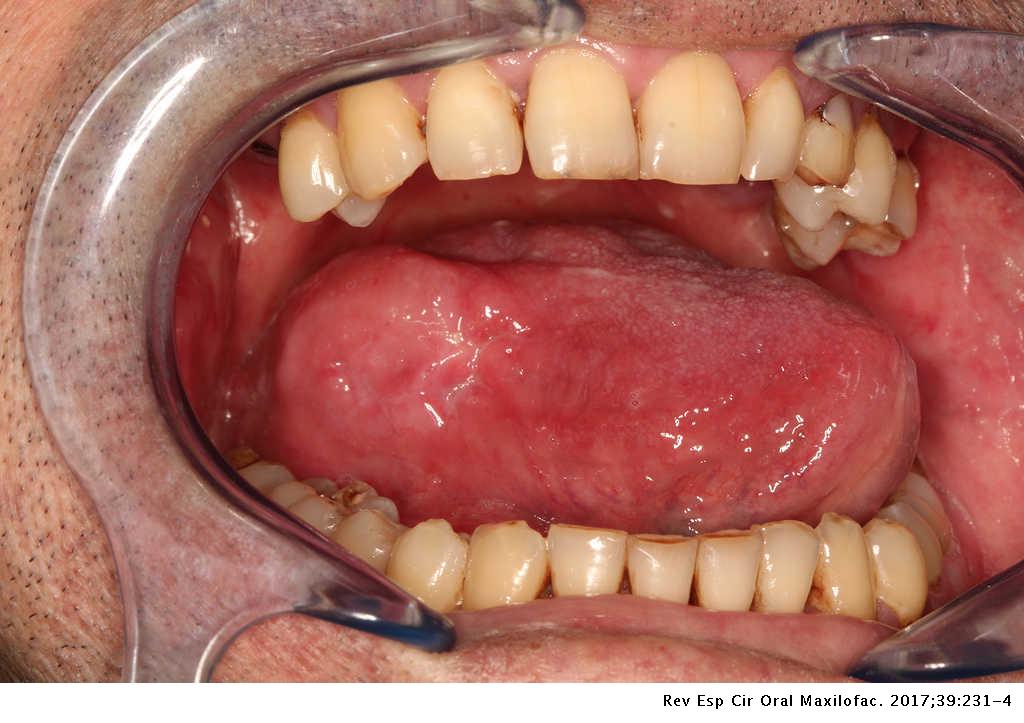

Leiomyosarcoma Of The Tongue A Rare Case Report Revista Espanola De Cirugia Oral Y Maxilofacial